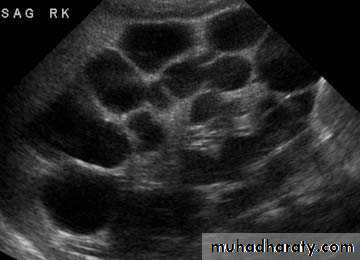

Poly cystic disease

Adult typePresent after the third decade of life , Familial.

Renal parenchyma is replaced by numerous cysts containing fluid , The cysts are of variable size ,

Clinically renal colic, loin mass , heamaturia and hypertension, Renal tissue interposed between the cysts after time dssimcted ended with renal failure

Almost bilateral.

IVU

Large kidney .

Lobulated out-line.

Distortion of pelvi- calyceal system depend on cyst size, number and position.

In advanced cases there is elongation and stretching of minor and major calyces ( spider leg).

In advanced cases IVU shows non-functioning kidney .